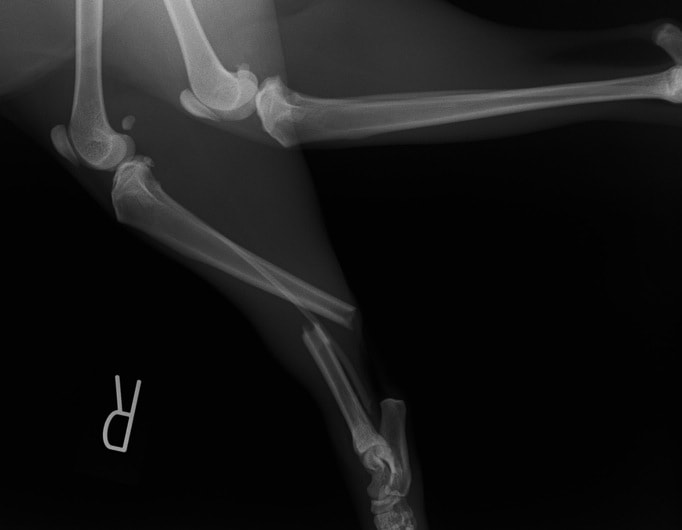

ペルシャ猫 11ヶ月齢 雄

他院にて左大腿骨遠位の成長板骨折(salter-harrisⅠ型)が認められており、治療相談を目的として来院。当院にて、キルシュナーワイヤーを用いたピンニングにより骨折部位の整復を行いました。術後の経過は良好で、現在も経過観察中です。

術前レントゲン

術後レントゲン